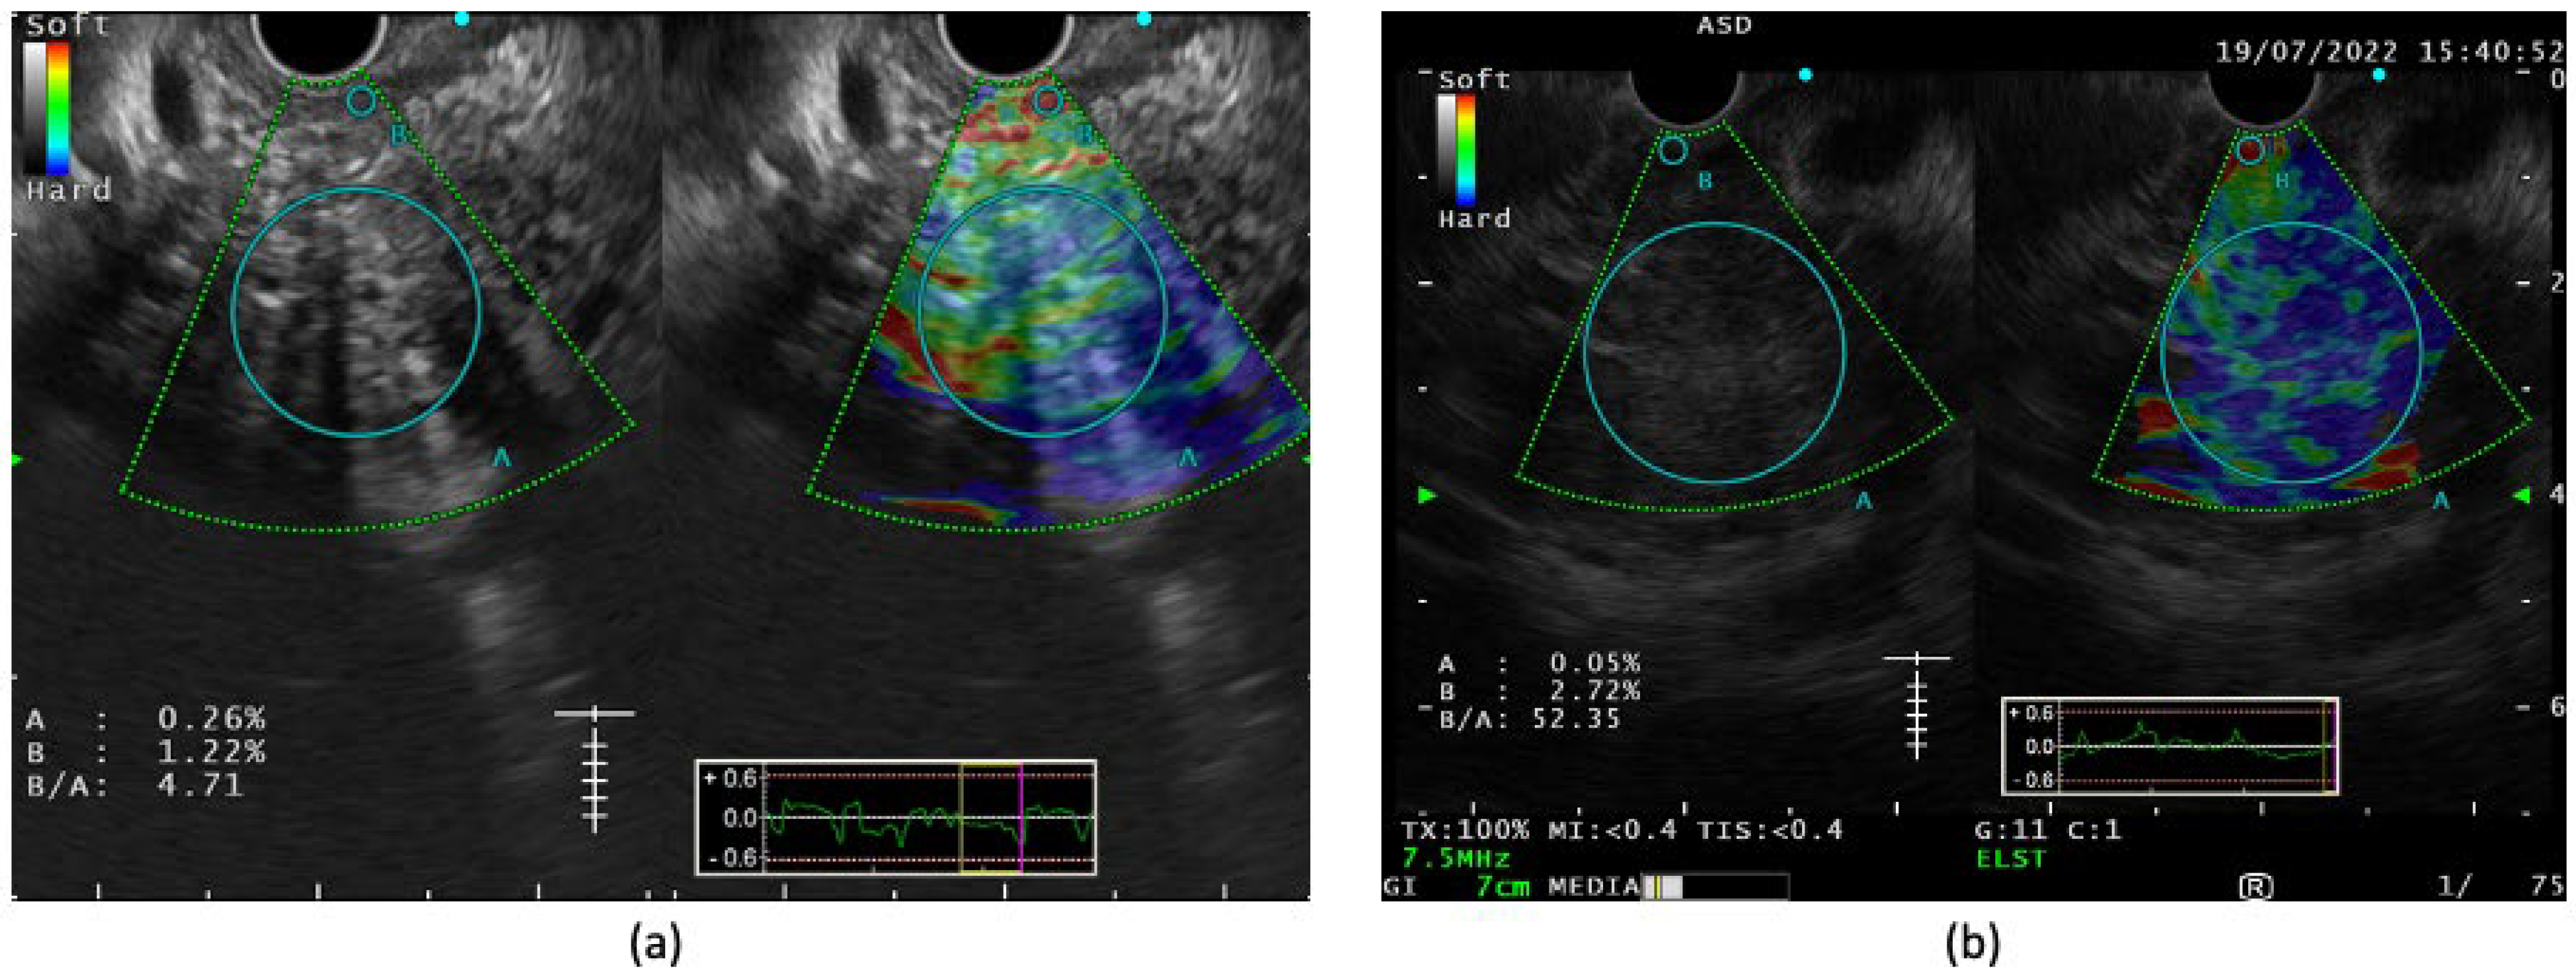

4. Role of Contrast-Enhanced EUS

5. EUS Elastography